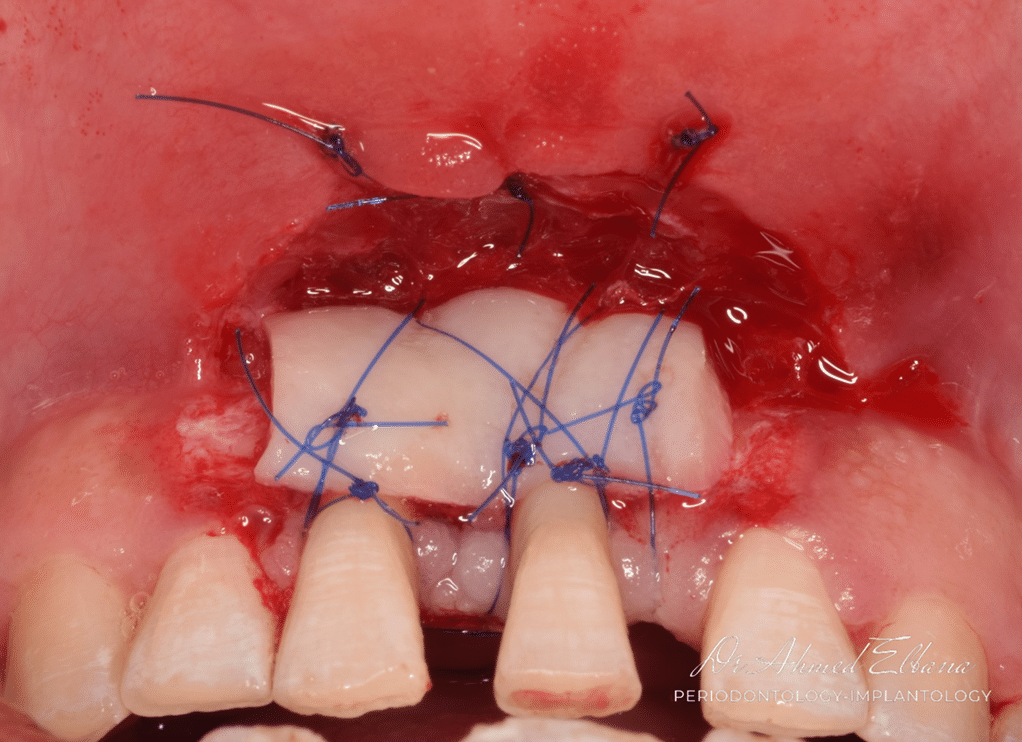

3- Harvesting FGG.

4- Graft adaptation.

FGG was harvested from the palate at the premolar region. partial thickness palatal graft was adequate for the treatment purpose.

the palate was sutured using collagen sponge and cross mattress sutures.

perfect adaptation is essential for plasmic diffusion which is mandatory for graft integration.

the size of the graft is preferred to be smaller than the recipient bed to ensure vascularization into the graft from all directions